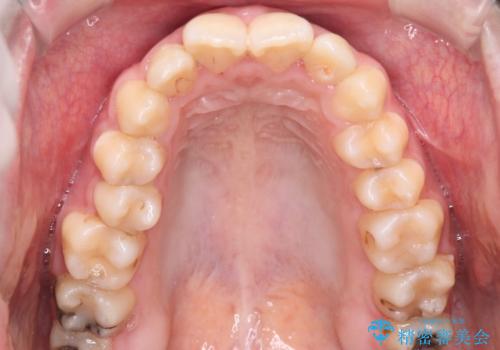

【ハーフリンガル】口元を下げたい!

- 口元が出ていることを主訴に来院されました。

歯を抜いてスペースを作ることで、前歯を下げることができました。

ハーフリンガルということで治療期間が3年近くかかりましたが、口元もしっかり下がり満足していただきました。